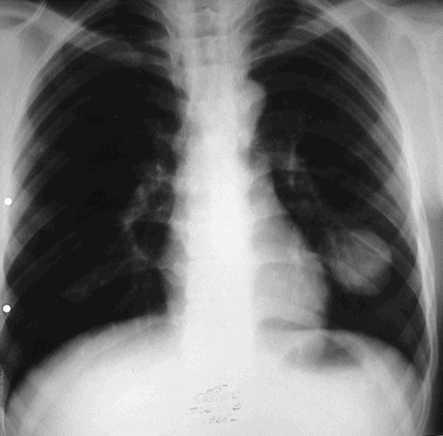

Эхинококкоз легких